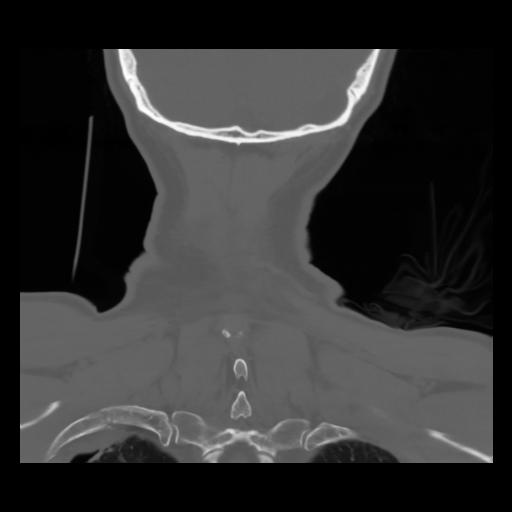

13 P.BLANDAS,,Coronal,2.000,P.BLANDAS,Coronal,